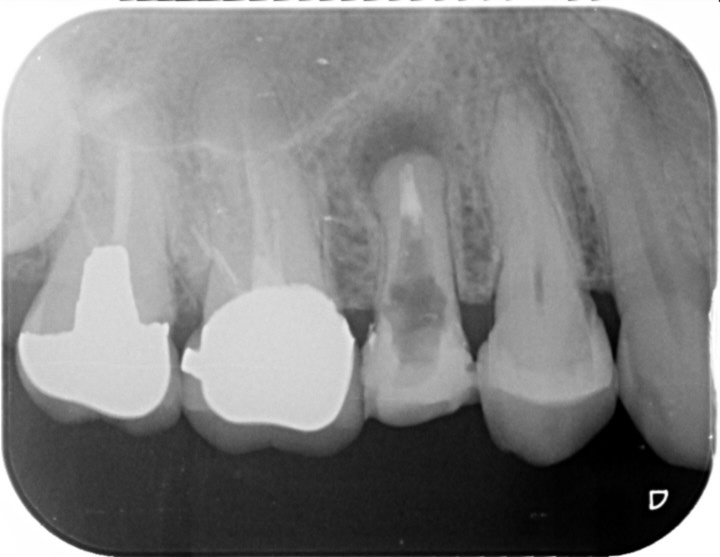

画像

R5.5

治療部位 左下6,7

費用 約700000円

治療期間 約6ヶ月

痛み、腫れを感じておりレントゲンを撮影、歯が破折している可能性がありました。

被せ物を外しヒビが確認されなければ根管治療で歯を残せる可能性があること、

ヒビがあった場合は抜歯になってしまうと説明しました。

このケースは残せる状態ではなく抜歯という選択になりましたが、できるだけ患者様のご希望に寄り添い、

治療計画をご提案できるよう最善を尽くしております。